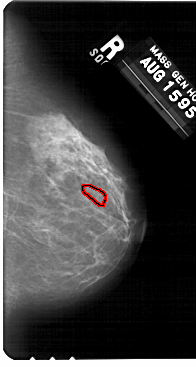

A_1310_1.RIGHT_CC

RIGHT_CC LINES 5491 PIXELS_PER_LINE 2926 BITS_PER_PIXEL 12 RESOLUTION 43.5 OVERLAY

FILE: A_1310_1.RIGHT_CC.OVERLAY

TOTAL_ABNORMALITIES 1

ABNORMALITY 1

LESION_TYPE CALCIFICATION TYPE PLEOMORPHIC DISTRIBUTION CLUSTERED

ASSESSMENT 4

SUBTLETY 1

PATHOLOGY BENIGN

TOTAL_OUTLINES 1

BOUNDARY